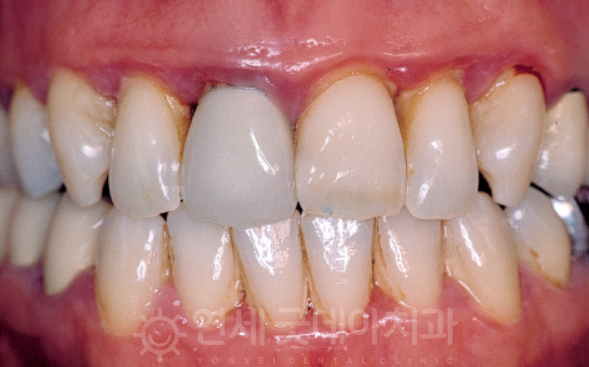

CASE 3 - 조직유도재생술

조직유도재생술 과정

마지막으로 살펴볼 것은 조직유도재생술 과정입니다.

사실, 많은 환자 분들이 잇몸이 흔들린다는 이유로

내원해 주시는데요. 이때 보면 잇몸과

잇몸뼈가 녹아있는 상태가 대부분입니다.

때문에 치아가 흔들리는 현상이 일어나게 되고,

이때 조직유도재생술을 고려하게 됩니다.

이는 잇몸병으로 인해 치조골이 불규하게

녹아내린 경우, 녹아내린 치조골 부위에 인공뼈나

자가골을 이식해 새로운 치주조직이 자라날 수 있도록

유도하는 치료법인데요. 잇몸이 자라서 들어가지

못하도록 차폐막을 사용하게 되며 치주판막수술이

동반될 수 있습니다.

이 치료법은 모든 분들에게 해당되기는 어려우나

잇몸이 녹아있는 양상이 재생이 가능한 경우라고

판단이 되면 조직유도재생술을 통해 회복을

기대할 수 있답니다.